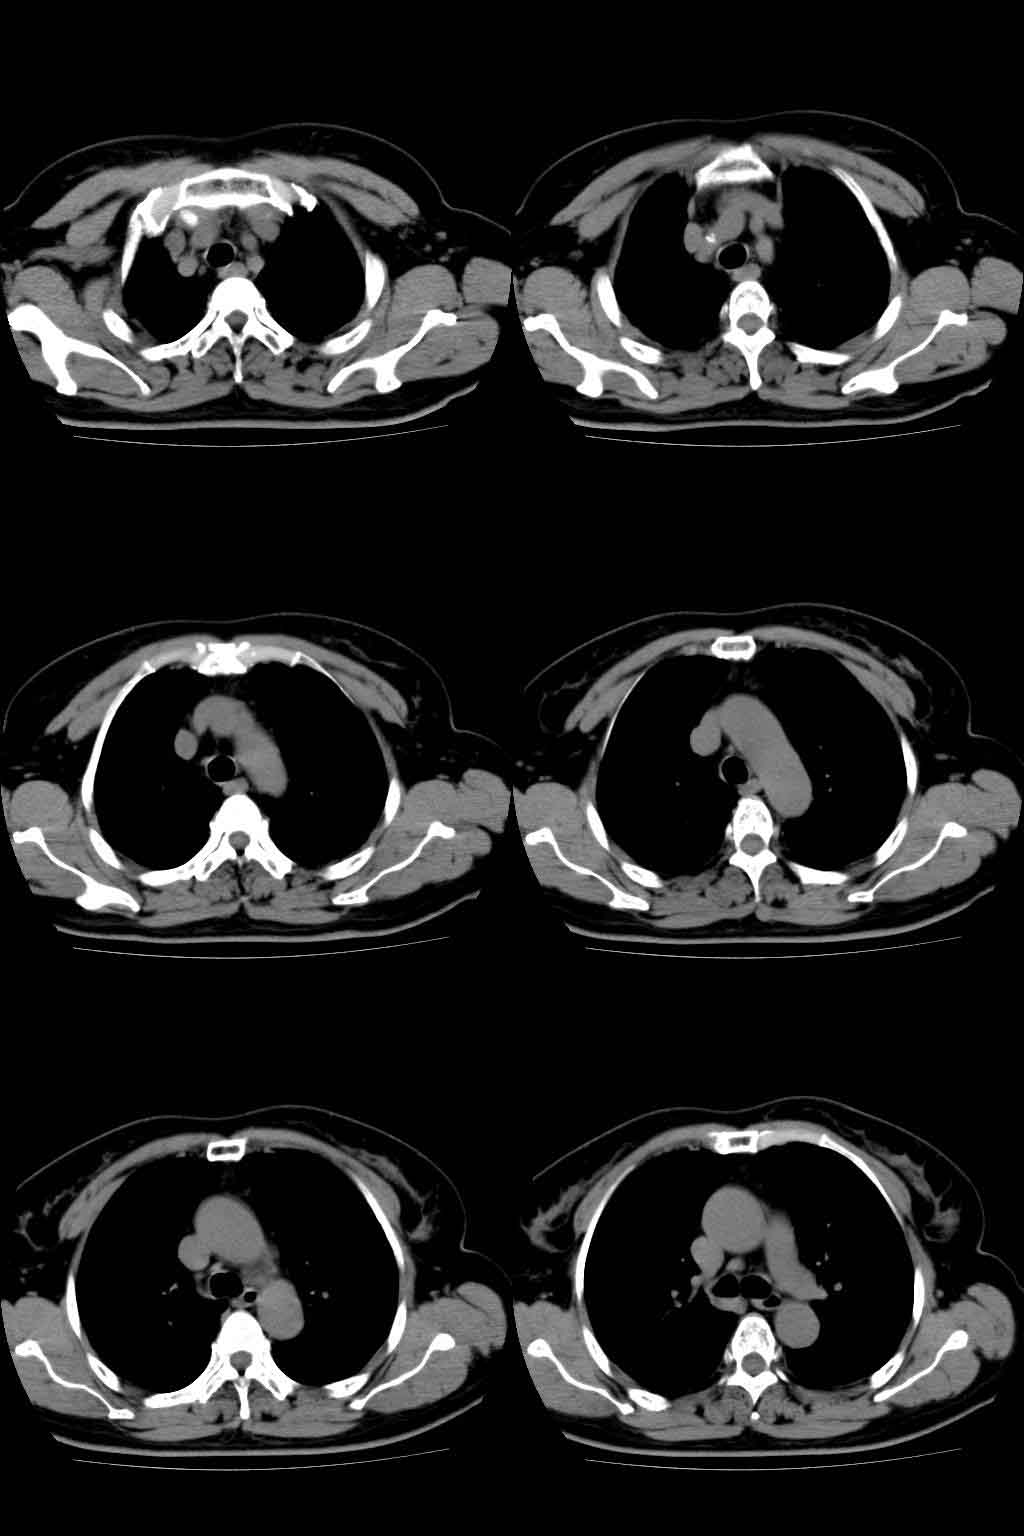

以下是引用lkc8963在2008-10-4 22:24:00的发言:[br]右下肺内基底段不规则软组织结块,肿瘤可能,建议增强鉴别于血管.